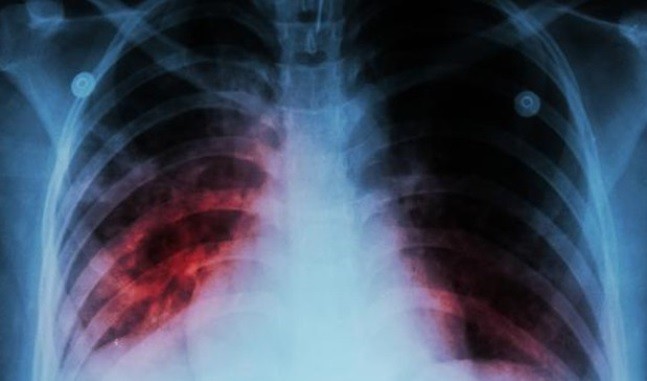

La enfermedad de tuberculosis.

La tuberculosis, enfermedad causada por la bacteria Mycobacterium tuberculosis, ha causado más muertes que ninguna otra enfermedad infecciosa a lo largo de la historia y se estima que en los últimos dos siglos ha costado la vida a más de mil millones de personas.